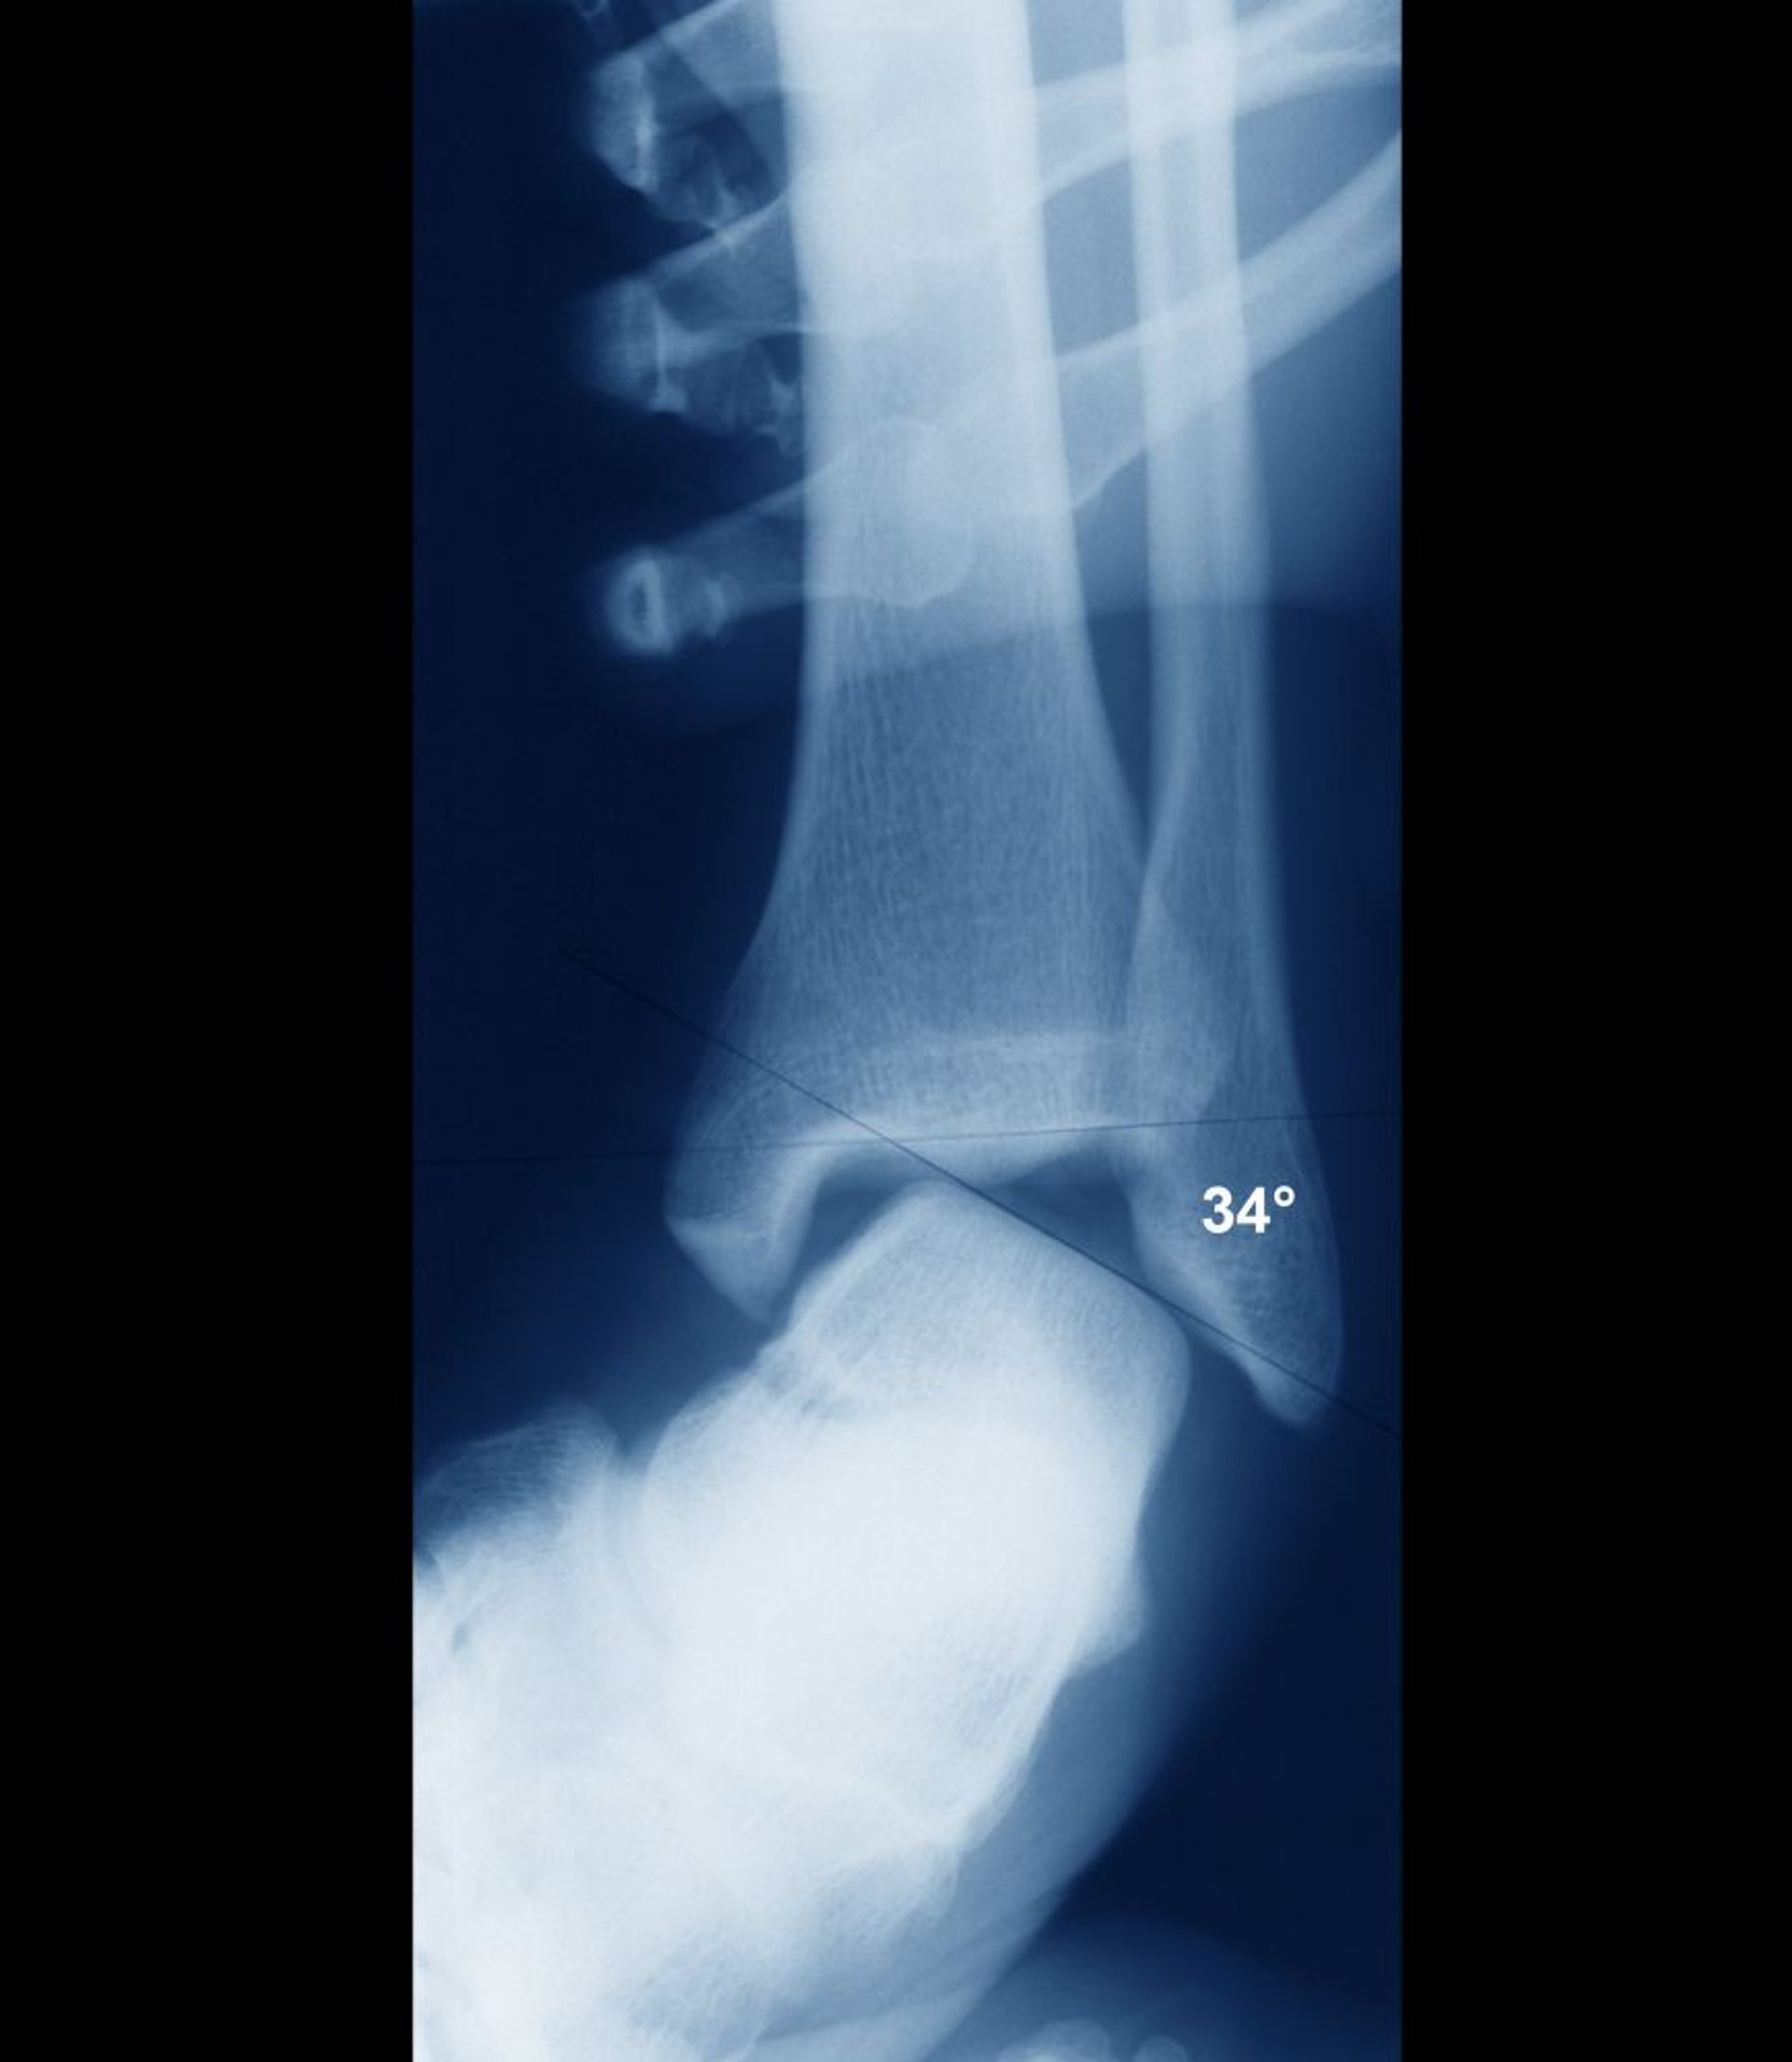

Entorse do tornozelo com instabilidade

Se o tornozelo estiver estável, as superfícies intra-articulares do talo e da tíbia devem estar paralelas. Aqui elas estão significativamente desalinhadas, indicando instabilidade articular flagrante. A instabilidade seria de evidente clinicamente, e a instabilidade costuma ser avaliada clinicamente, sem a necessidade de radiografias.